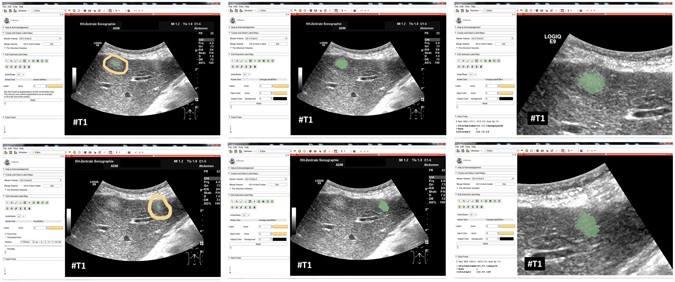

Ultrasound acquisitions have been performed by using a multifrequency curved probe. The US probes LOGIQ E9 and Aplio 80 from GE Healthcare (Milwaukee, Il, USA) and Toshiba (Otawara, Japan), respectively, allowed image scans with a bandwidth of one to six MHz. Fulfilling the following criteria, images have been selected retrospectively from the digital picture archive of the Katharinenhospital Stuttgart (Germany) ultrasound unit. Regarding the first part of the study, where the algorithm was adjusted using images with different echo pattern, ultrasound examinations of patients treated for different malignancies were chosen. The main selection criteria consisted of the echogenicity class of the lesion, which could be hypo-, hyper or isoechoic. The selection process was stopped when one lesion per echogenicity class was identified. Additional three images with metastases of different echogenicity were used in the first part of this study to visualize the performance of the algorithm. The selection of 40 images in the second part of the study for the evaluation of the algorithm was done by choosing ultrasound examinations of consecutive patients treated for metastatic pancreatic cancer. However, we excluded images were text or markers overlaid the target lesion. Afterwards, we removed the patient information from the image, and the anonymized image was segmented with our algorithm. The local ethical committee from the Katharinenhospital, Stuttgart, Germany, provided a waiver of the requirement for informed consent for this retrospective study and allowed the publication of anonymized data. Note, we added figure serial numbers to the images in the lower left corners. Cases we used to develop, test and present our algorithm in the first part of the manuscript are indicated with #T followed by a number, e.g. #T1 in in Fig. 2. The 40 cases we used to evaluate our algorithm are indicated with #E followed by a number from 1 to 40, e.g. #E39. The anonymized raw data can be used for own research purposes as long as our work is cited27: https://www.researchgate.net/publication/307907688_Ultrasound_Liver_Tumor_Datasets.

Our segmentation algorithm was integrated into the medical prototyping platform MeVisLab (Fraunhofer MeVis, Bremen, Germany, www.mevislab.de) as a C++ module33, 34. The interactive real-time segmentation could be performed smoothly on a Macbook Pro laptop with an Intel Core i7-4850HQ CPU @ 2.30 GHz, 16 GB RAM and Windows 8.1 Professional installed. The adjustment of our segmentation algorithm was done using a set of liver metastases with different echo pattern. For visual inspection, Fig. 7 shows an interactive and a manual segmentation result of a liver metastasis (metastasis of a colon cancer) that appears brighter (hyperechoic), when compared to the surrounding liver tissue. Further, the metastasis has a darker (hypoechoic) halo and exhibits a very low contrast to the surrounding liver parenchyma. Overall, the leftmost image of Fig. 7 presents the native acquisition with a zoomed area of the metastasis. The image in the middle of Fig. 7 shows the manual measurement result of the metastasis (white dotted line between two crosses). Finally, the rightmost image of Fig. 7 presents the interactive segmentation results and the user-defined seed point at this position (red dots and white dot, respectively). In Fig. 8, the interactive segmentation results of several liver metastases (red dots) are presented as follows: Upper Left: a metastasis of a neuroendocrine neoplasm of the pancreas. Upper right: a metastasis of a colon cancer. Lower images: two different views of a metastasis of a uveal melanoma. Compared to the surrounding liver tissue, the metastasis in the upper left image appears brighter (hyperechoic). In contrast, the two metastases in the lower images appear darker (hypoechoic) when compared to the surrounding liver tissue. Finally, the metastasis of the upper right image has bright and dark areas in comparison to the surrounding areas. For all segmentation results of Fig. 8, the white dots represent the corresponding seed points. At these positions, the user was satisfied with the borders of the lesion and stopped the interactive segmentation process by releasing the mouse button.

Segmentation results for different liver metastases (red dots). Presented are a hyperechoic metastasis of a neuroendocrine neoplasm of the pancreas (upper left), an isoechoic metastasis of a colon cancer (upper right) and two different views of a hypoechoic metastasis of an uveal melanoma (lower images). The white dots in the images are the user-defined seed points. At this positions the user stopped the interactive segmentation, because (s)her was satisfied with the automatic segmentation of the metastasis border. Note: figure adapted from26.